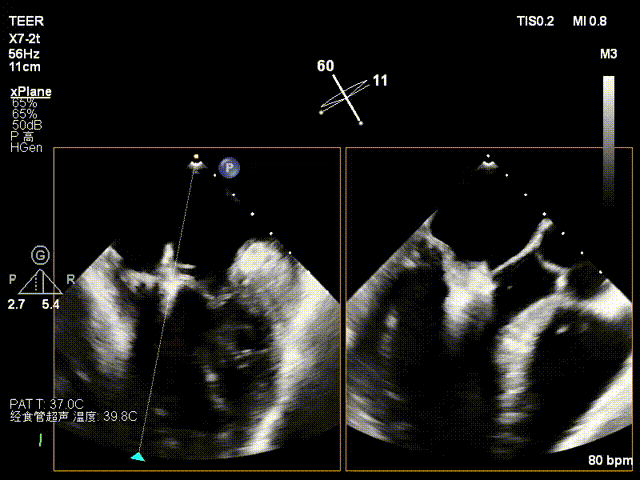

患者为73岁老年男性,经食道超声检查提示:急性二尖瓣腱索断裂合并反流,前叶长度:2.8cm,后叶长度:1.7cm,脱垂宽度:18mm,脱垂高度:8mm,瓣口面积:6.5cm²。

术前影像

左房极小

房间隔增厚

X-plane2区

X-plane2区彩色